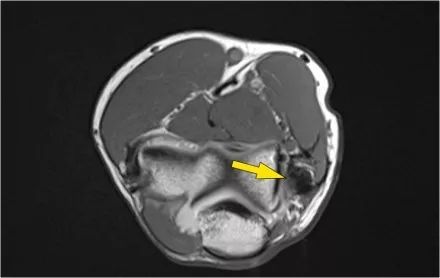

二头肌腱:从肌腱连接处到径向结节上的附着物。

远端肱二头肌肌腱的病理学很像跟腱的病理学。可以有退变,部分撕裂和完全撕裂带或不回缩。以下是73岁男性的超声图像,他们在举起一个盒子时经历了突然的疼痛和撕裂的感觉。在肘关节前方有前旋和旋后疼痛,前方有压痛。

没有瘀斑或可触及的肿块。在矢状图像上,肌腱变厚,但远端肌腱丢失。

在矢状图像上,看起来肌腱完全是刺,但继续下一个图像。

● 远端肱二头肌肌腱撕裂:有完全撕裂,因为如果我们一直跟随肌腱进入桡骨结节,我们可以看到肌腱不附着在那里(绿色箭头)。只有流体。● 肌腱不缩回的原因是因为广泛的萎缩性肌腱 - 也被称为lacertus fibrosus - 仍然完好无损(红色箭头)。● 远端肱二头肌肌腱不仅插入到桡骨结节,而且还通过褶皱纤维进入前臂内侧屈肌旋前肌块的筋膜。

当腱膜也thorn时,肌腱缩回,并且由于收缩的二头肌造成手臂明显肿胀。远端二头肌肌腱撕裂是一种罕见的损伤。大约有5%的肱二头肌受伤。这是肘部弯曲时手臂突然伸展的结果。近端肱二头肌腱撕裂更常见。通常是二头肌的长头完全撕裂。

下面这是另一个例子。在T1W图像上有一些增厚和一些中间信号。这可能是肌腱变性,但总是看T2W图像寻找撕裂。在这种情况下,有部分撕裂。

下面是另一种情况。在矢状图像上,我们不确定可能的撕裂。也许只有一些肌腱炎或肌腱炎。轴向图像显示部分撕裂(红色箭头)。

始终确保你的轴向扫描一直到结节,因为你太早停止,就像在这种情况下,你只会看到增厚的肌腱和一些液体,但你不确定可能的撕裂。